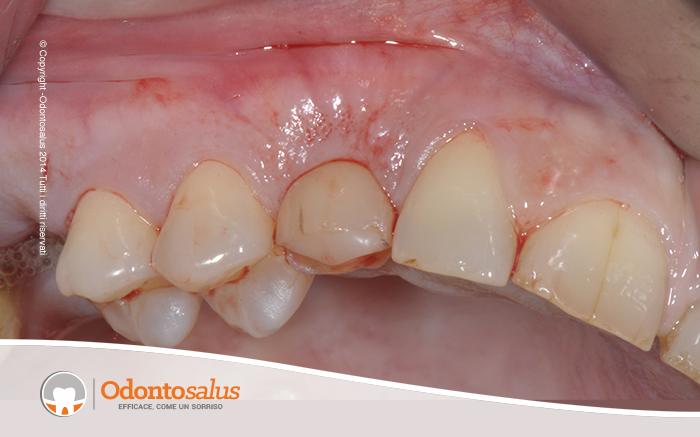

Il paziente si presenta in studio con il canino in inclusione (elemento 13).

Inizialmente è stato effettutao un trattamento ortodontico per riportare l’elemento incluso in arcata. Tuttavia, come a volte accade in relazione all’età del paziente, alla densità ossea o alla posizione del dente incluso, ortodonticamente non è stato possibile riallineare il canino con gli altri denti. Si è proceduto, pertanto, con l’incisione del lembo, la scopertura e l’estrazione del canino, il riempimento del deficit osseo creato, l’applicazione dell’impianto e, data la sua stabilità, l’inserimento del provvisorio nella stessa seduta.